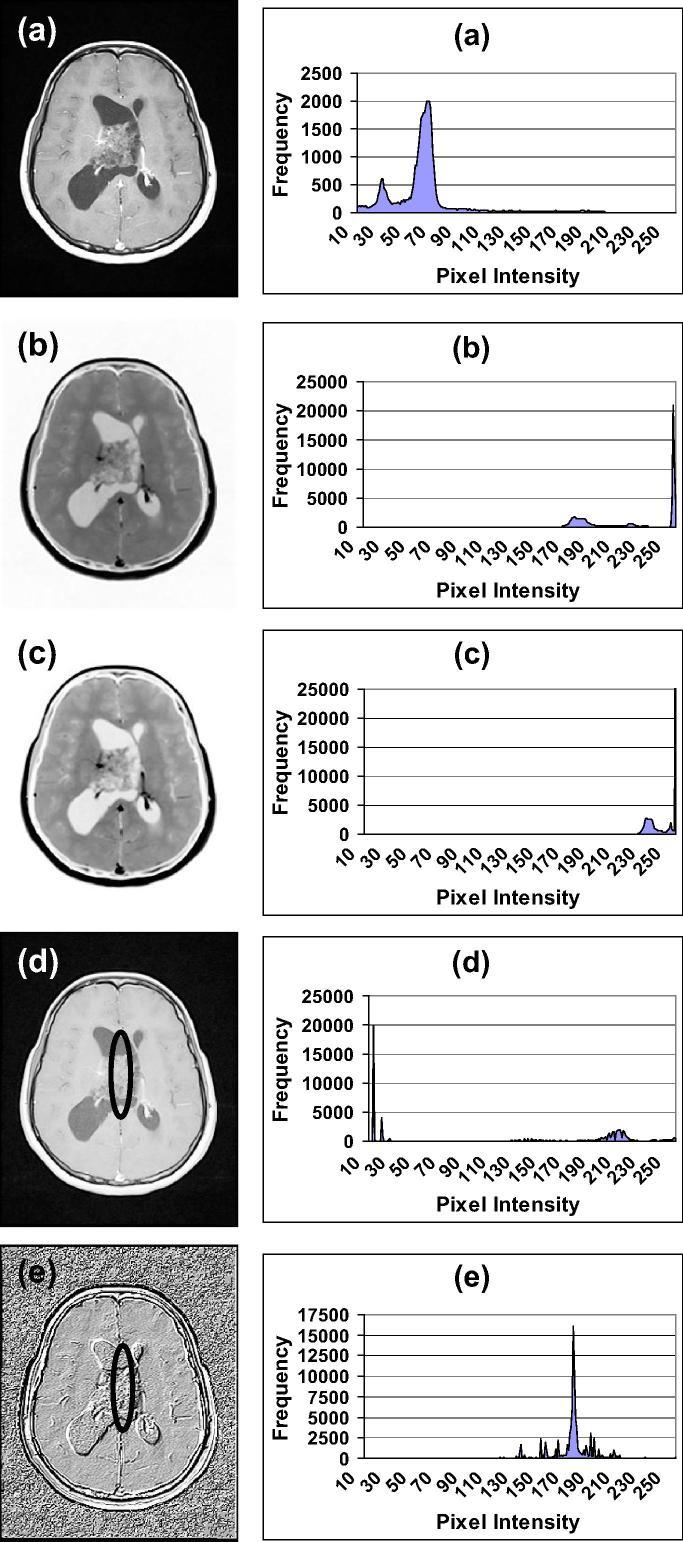

This research presents signal-image post-processing techniques called Intensity-Curvature Measurement Approaches with application to the diagnosis of human brain tumors detected through Magnetic Resonance Imaging (MRI). Post-processing of the MRI of the human brain encompasses the following model functions: (i) bivariate cubic polynomial, (ii) bivariate cubic Lagrange polynomial, (iii) monovariate sinc, and (iv) bivariate linear. The following Intensity-Curvature Measurement Approaches were used: (i) classic-curvature, (ii) signal resilient to interpolation, (iii) intensity-curvature measure and (iv) intensity-curvature functional. The results revealed that the classic-curvature, the signal resilient to interpolation and the intensity-curvature functional are able to add additional information useful to the diagnosis carried out with MRI. The contribution to the MRI diagnosis of our study are: (i) the enhanced gray level scale of the tumor mass and the well-behaved representation of the tumor provided through the signal resilient to interpolation, and (ii) the visually perceptible third dimension perpendicular to the image plane provided through the classic-curvature and the intensity-curvature functional.